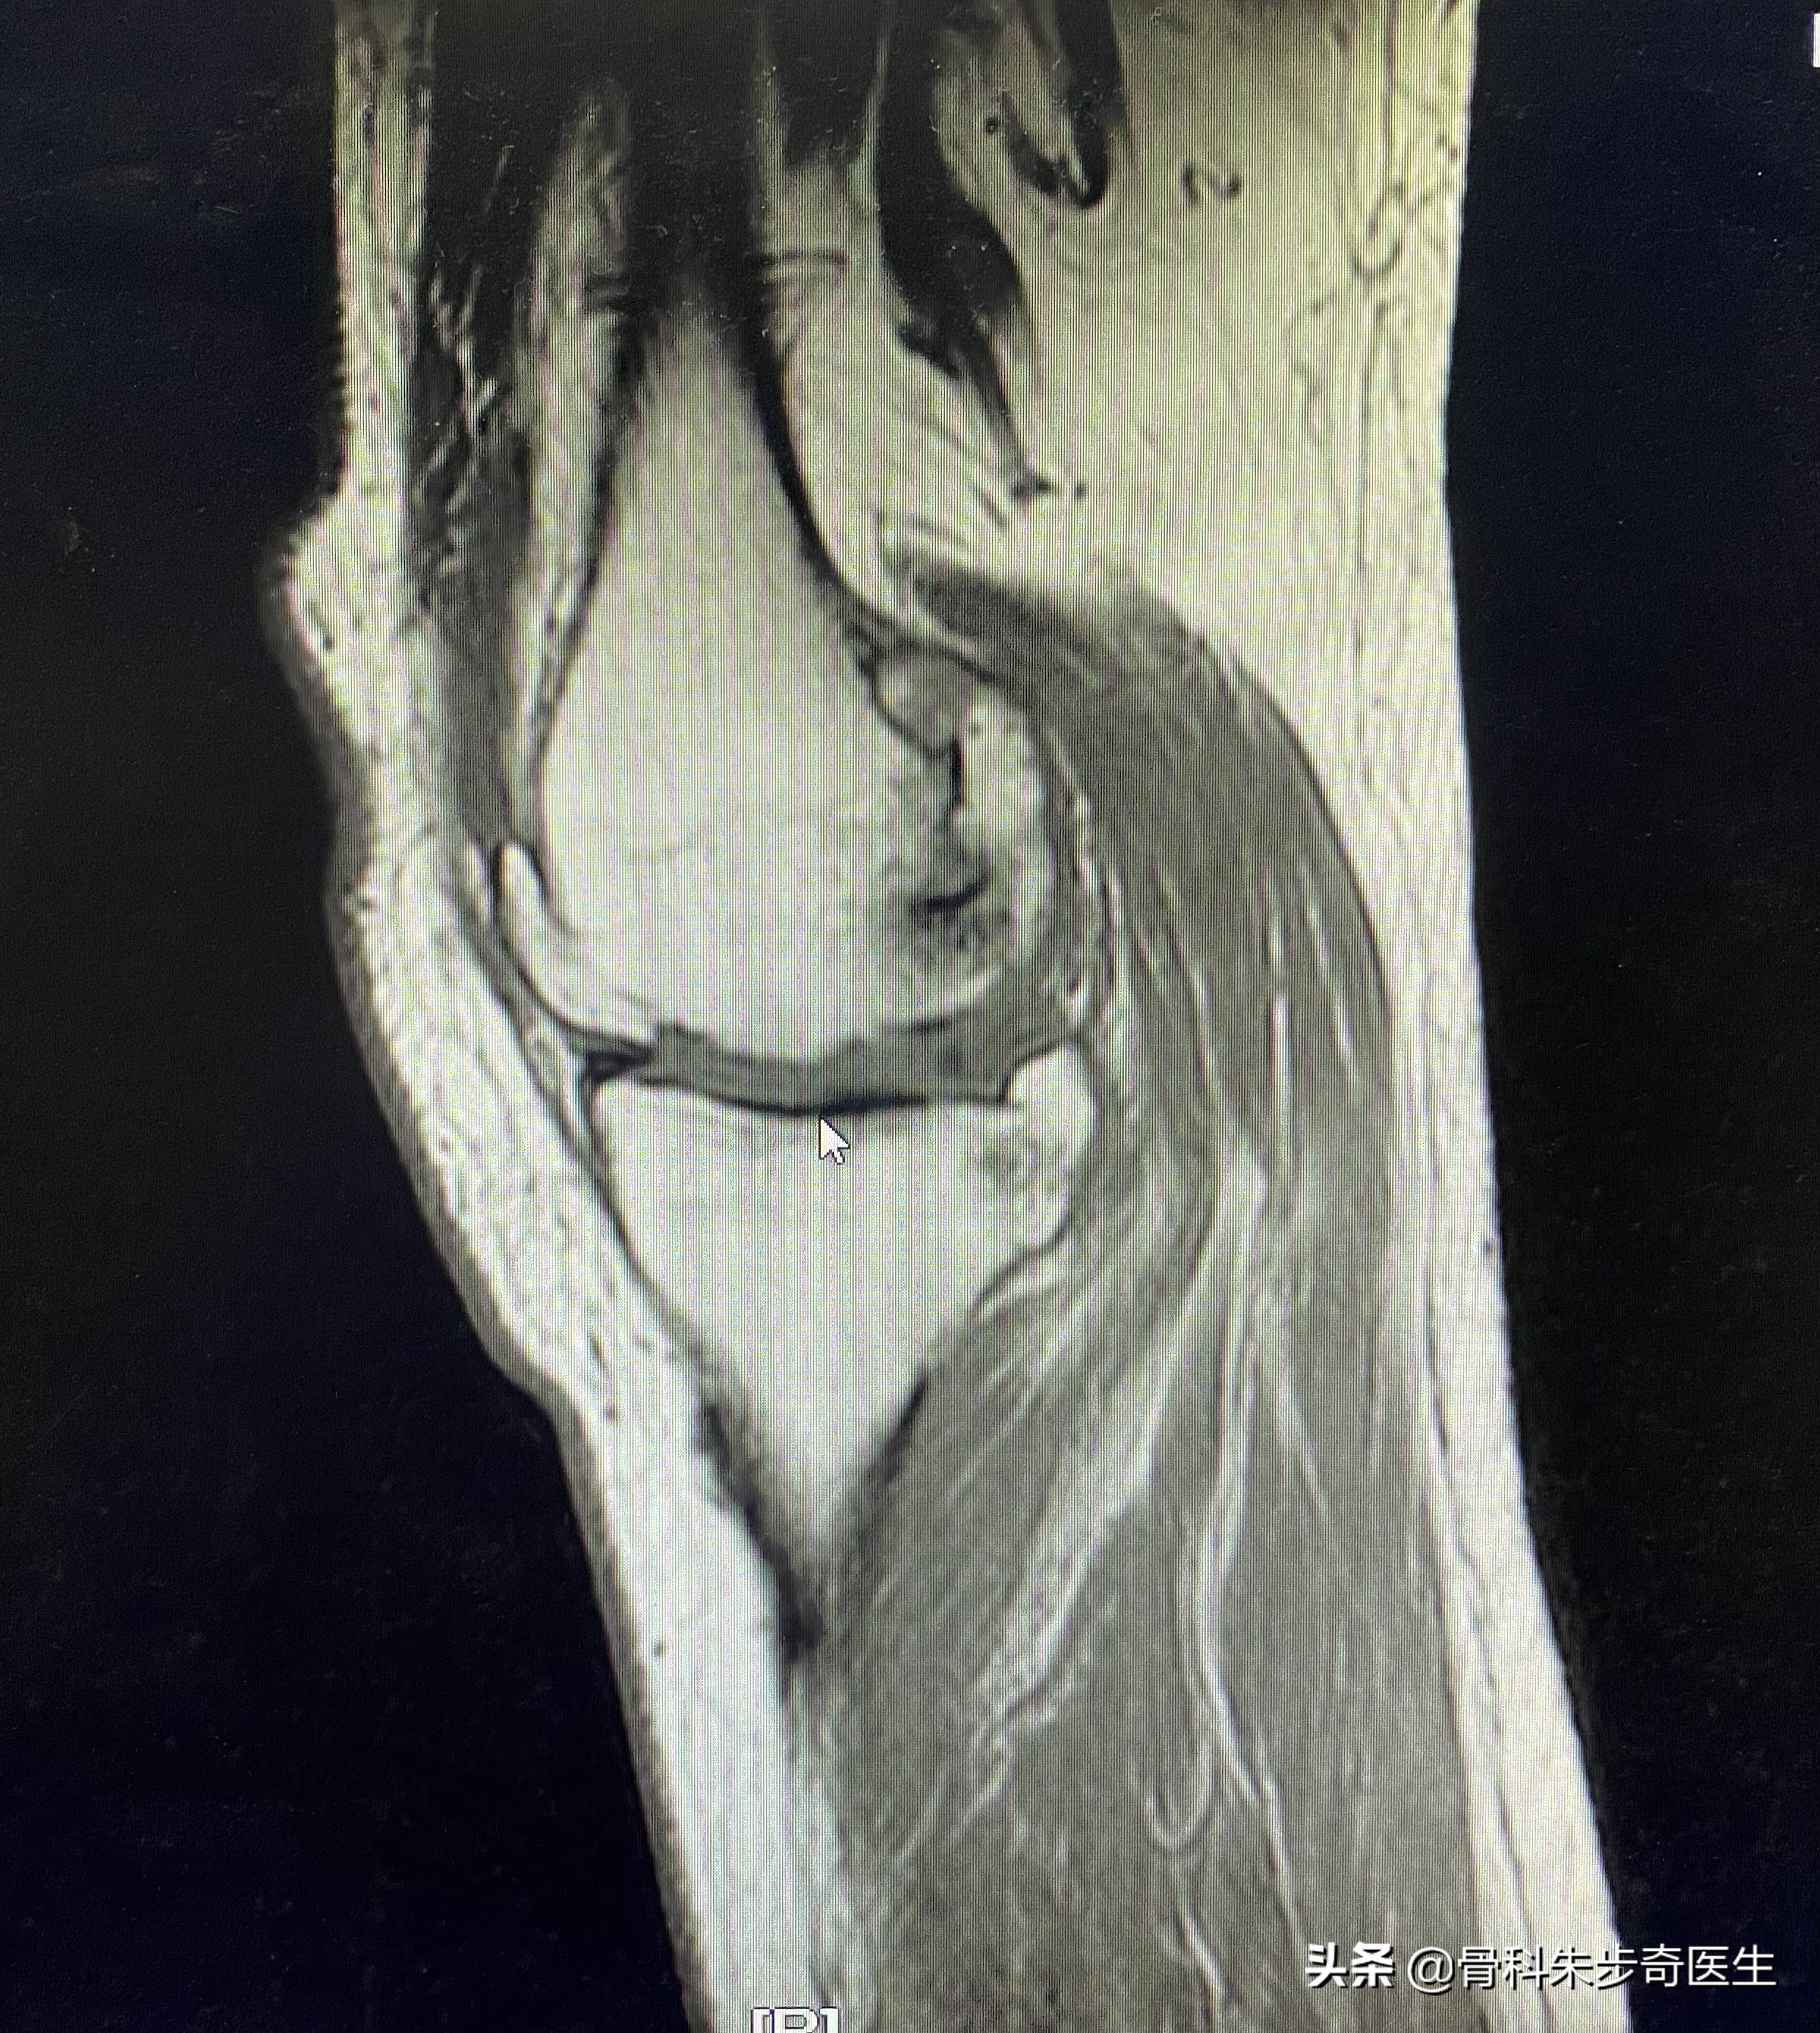

住院之后为了进一步搞清楚膝关节内部的问题,又做了一个核磁共振,结果如下:

看起来问题挺多,其实不管是软化,还是半月板撕裂,游离体,滑膜增厚,这些其实都是关节退变的表现。

根据这个情况,比较适合的是关节镜治疗,需要用关节镜把游离体取出来,同时观察膝关节内部的软骨,和滑膜情况,还可以清理一下内部的关节,所以建议她做膝关节的关节镜。